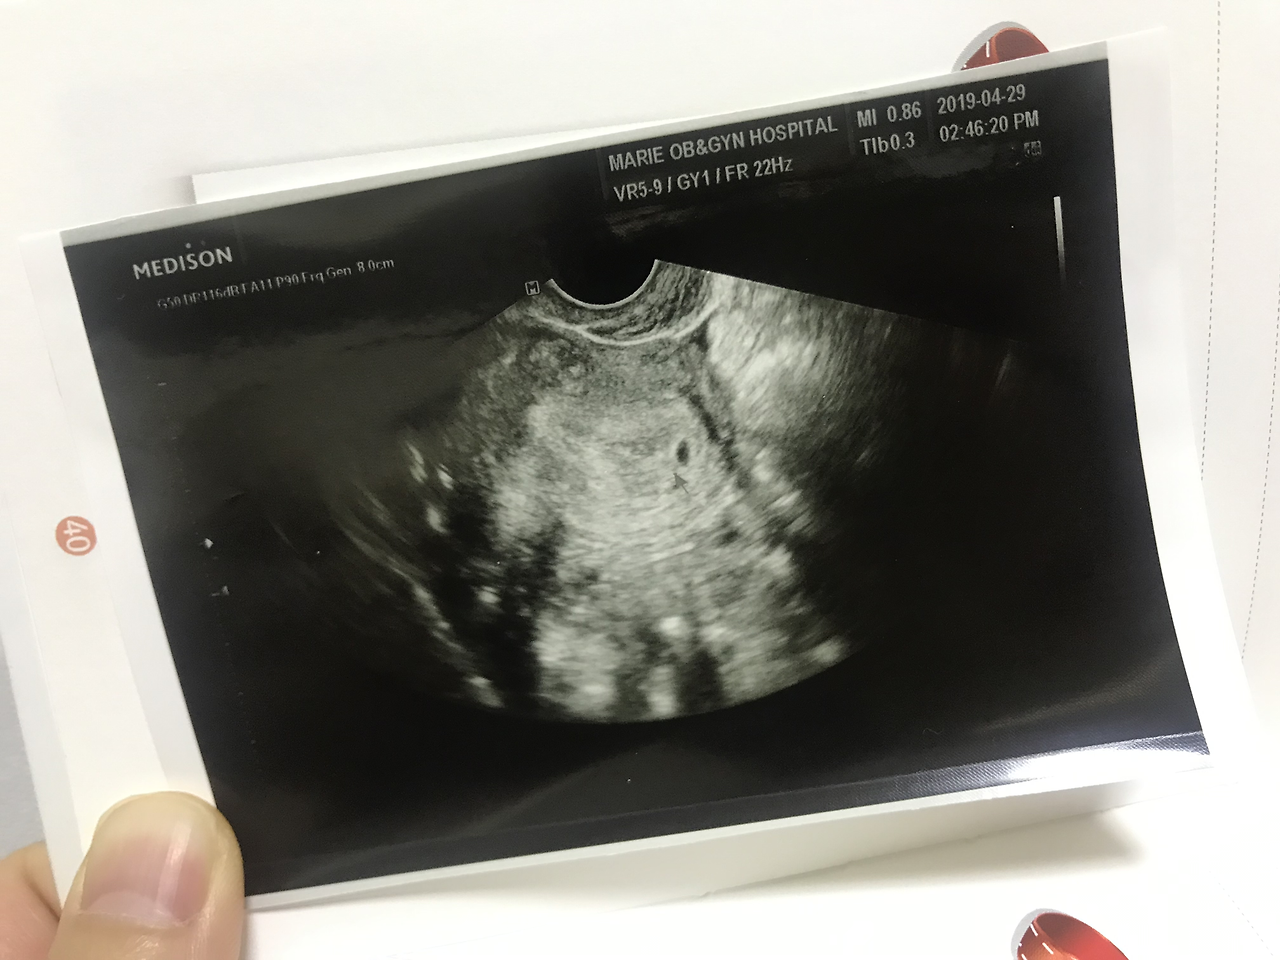

그렇게 이틀이 지나고 너를 처음 만나게 됐어. 의사 선생님은 4주에서 5주 정도 되었다고 하셨어. 쿵쾅쿵쾅 쿵쾅 0.36cm, 점처럼 자그마한 너에게서 뿜어져 나오는 심장소리를 듣는 순간, 울컥하면서 눈물샘이 터지고야 말았어. 얼마나 세차게 뛰는지 엄마 심장도 덩달아 쿵쿵거렸어. 엄마가 임신 사실도 모른 채 지독한 감기몸살에 시달리고, 또 교토에서는 하루 종일 며칠을 꼬박 걸어 다녔는데 그걸 다 견뎌주다니.. 얼마나 기특한지 몰라. 벌써부터 씩씩함이 느껴지는 우리 달이. 지금부터 엄마랑 아빠랑 함께 파이팅 해 보자.